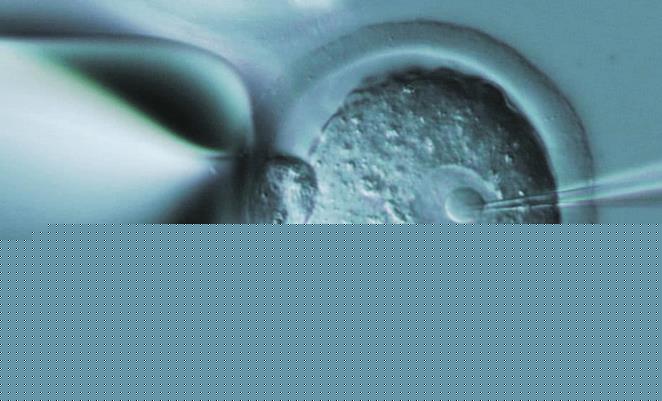

试管婴儿手术成功率对于每一个患者而言都是非常重要的,患者在做这项手术的时候肯定也在思考,同样都是做手术,为什么不选择一个成功率相对较高的医院,毕竟这对患者本身来讲会带来更多保障。山东临沂做试管婴儿成功率最高的医院是哪里?这也是每一个患者希望能够提前了解的,当我们在选择试管婴儿这项手术的时候,一定要具体情况具体分析,只有这样才能给我们带来一系列体验。

患者在临沂地区选择试管婴儿医院的时候,建议患者最好能够综合考察,并不是说成功率较高的医院就一定适合患者,每一位患者在做试管婴儿之前肯定就会到医院做检查,在做检查的时候,最起码能够了解到自己的身体状况,会了解到自己究竟是什么原因所导致的不孕不育,比如如果是因为女性原因导致的不孕不育,那么我们在选择试管婴儿医院的时候,就要选择这方面案例相似的情况,这样才能给我们带来诸多保障。

山东省妇幼保健院生殖中心试管成功率约40%-51%,近年来生殖中心辅助生殖周期逐年增长,保持较高的成功率,但试管成功率最终取决于取卵结果和胚胎质量,以下依据14颗基础卵泡数量预测到山东省妇幼保健院做试管成功率,可参考下表: